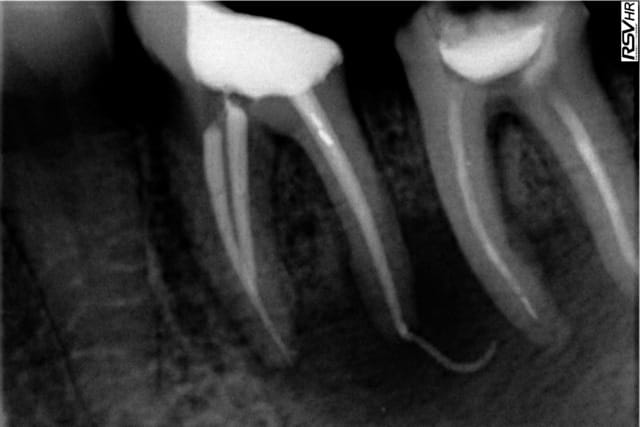

19/09/2012 à 14h03

Patient 45 ans CMU, 37 avec un énorme abcès, j'ouvre, je draine, la lime 30 va directement aux apex (d'après mon localisateur) et au-delà (d'après la radio) "on va essayer de sauver la dent mais franchement, ça m'étonnerait qu'on y arrive."

hydroxyde calcium à la fin du premier rdv quand ça s'est à peu près arrêter de suppurer.

deuxième rdv, après à peu près 20 minutes à essayer de calibrer mes cônes à la longeur de travail, je les sens bien buter à l'apex "cool, je croyais que j'y arriverais jamais"

Là, je prends Max et Spaden, vziouuuuu, radio, et meeeeerde "bon bah on va surveiller mais à mon avis faudra quand même extraire la dent"

Asymptomatique depuis un an ^^

Et puis évidemment, une boulette n'arrive jamais seul, exactement le même cas deux semaines après mais chez une patiente (même problème, même traitement, même résultat de merde, la pêche énorme d'origine en plus en mode "on va faire un traitement endo préimplantaire")